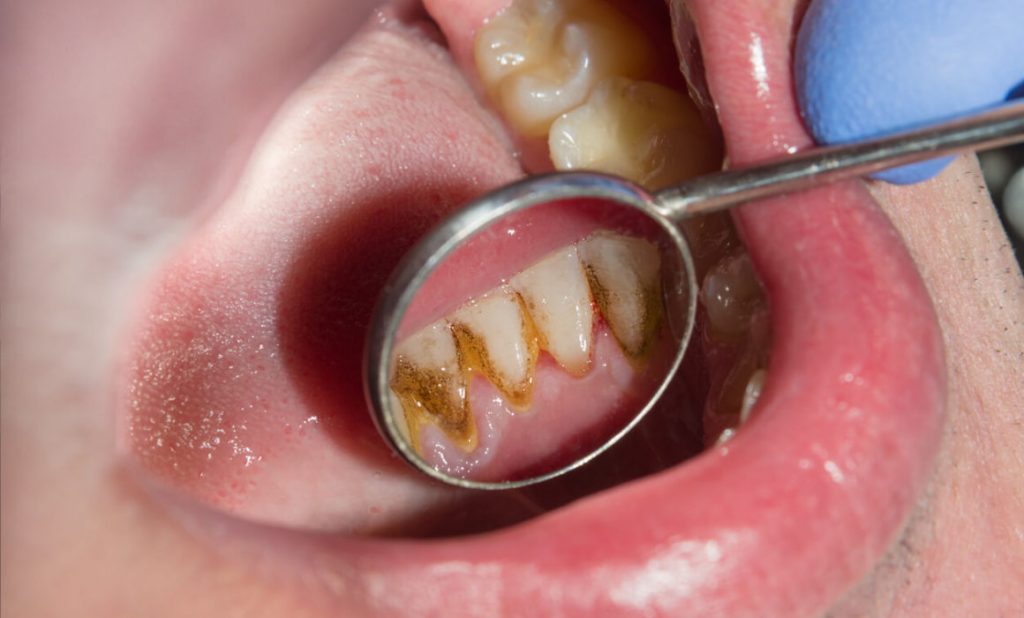

Diş tartarı temizleme işlemi için, evde uygulanabilen yöntemler olsa da kesin sonuç elde etmek için bir diş hekimine başvurulması gerekmektedir. Diş tartarı temizleme genel olarak anestezi gerektirmeyen ve uyuşturulmadan yapılan bir uygulamadır. Diş tartarı oluştuktan sonra, bunu diş fırçası ile uzaklaştırmanın imkânı bulunmamaktadır. Fakat diş eti, tartar oluşumundan önce birtakım belirtiler vermektedir. [caption id="attachment_6150" align="alignleft" width="401"]

diş tartarı temizleme[/caption] Dokunulduğunda kanayan; ödemli ve hafif kızarık diş eti, diş tartarı oluşumunun habercisi olabilmektedir. Bu belirtiler fark edildiğinde düzenli olarak dişlerin fırçalanması, gargara yapılması ve diş ipi kullanılması diş tartarı oluşumunu önlemede oldukça etkilidir.

Diş Tartarı temizleme, ağız hijyeninin yeterli olmaması nedeniyle, diş ve diş etlerinde oluşan plakların temizlenmesi adına yapılan işlemdir. Diş tartarları, dişlerde sarıdan kahverengiye dönen oldukça koyu renkli yapılardır. Plaktan farklı olarak diş ipi ya da diş fırçası ile temizlenmeleri söz konusu değildir. Diş tartarı diş minesine yapışık haldedir ve bu nedenle de mutlaka diş hekiminden yardım alınması gerekir.